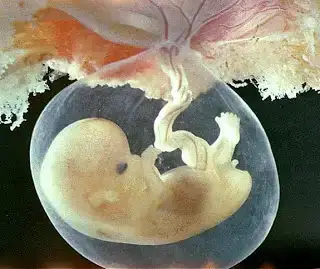

6.haftaya gırenlerrrrrrr bu hafta bebegınızde ki gelısımlerrrr

6 HAFTALIK GEBELİK (HAMİLELİK) GÖRÜNTÜSÜ

ALTINCI HAFTADA HAMİLELİK - BEBEĞİN BOYU, KİLOSU, BÜYÜKLÜĞÜ

Altı haftalık gebelikte bebeğin kalp atışları rahatlıkla ultrason muayenesinde duyulabilir ve görülebilir. Bebeğin boyu çok küçük 4-6 mm kadardır. Kilosundan bahsetmek henüz mümkün değildir. Bebeğin solunum ve sindirim sistemini oluşturacak ilk yapılar belirginleşir.

6. haftada bebeğin göbek kordonu oluşur. Gözler, kulaklar ve ağız boşluğu belirmeye başlar. Bebeğin beyni gelişmeye ve aktivite göstermeye başlamıştır. Bebeğin ileride kol ve bacaklarını oluşturacak tomurcuklar şimdiden belirginleşmeye başlar.